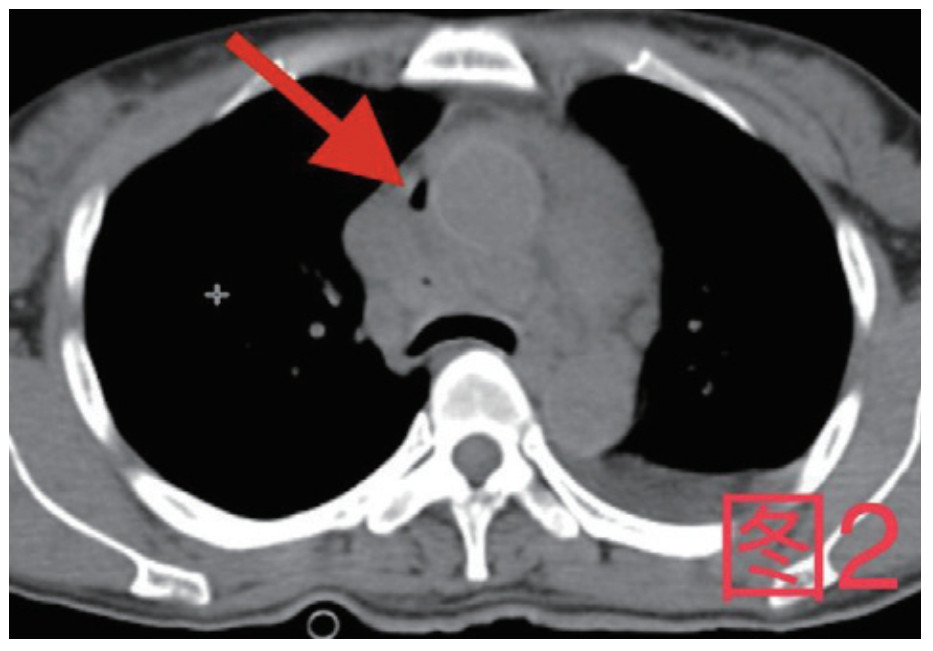

患者,女,41岁,2020年10月26日因“腹痛3 d”入急诊,否认近期有吞服异物、鱼刺、骨头等,无腹部手术史。入院查体:体温36.9℃,心率115次/min,血压98/57 mmHg(1 mmHg=0.133 kPa),血氧饱和度:97%;腹软,上腹部压痛,腹肌略紧张,余查体阴性。入院初检验:乳酸13.3 mmol/L;超敏C反应蛋白212.46 mg/L;血常规白细胞计数35.0×109/L,中性粒细胞百分数0.908,降钙素原50.46 ng/mL;Pro-B型钠尿肽7 117 pg/mL;肌钙蛋白T 0.147 ng/mL;肌酐554 μmol/L,谷丙转氨酶2 499 U/L,谷草转氨酶5 908 U/L。心电图未见ST-T改变;胸腹部增强CT(图 1图 2):示大量心包积液伴少许积气,纵隔少量积气;左侧少量胸腔积液,右肺下叶感染,盆腔少量积液;心脏超声:心包积液(大量),最深处21 mm;急诊予心包穿刺引流出大量浑浊脓性液体,心包穿刺引流液常规:中性粒细胞占96%,涂片见革兰阴性杆菌及革兰阳性球菌,积液培养见咽峡炎链球菌。诊断:化脓性心包炎,脓毒血症,多脏器功能不全,代谢性酸中毒。本病例报道经温州医科大学附属东阳市人民医院伦理委员会批准,且所有临床检测指标及有创操作均获得家属同意或直系亲属的授权(伦理审批号:东人医2021-YX-124)。

图 1 箭头所指为心包内积气积液

图 2 箭头所指为纵隔内积气